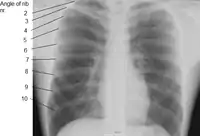

X-ray image of human chest, with ribs labelled

The first seven sets of ribs, known as "true ribs", are attached to the sternum by the costal cartilages. The first rib is unique and easier to distinguish than other ribs. It is a short, flat, C-shaped bone, and attaches to the manubrium.[6] The vertebral attachment can be found just below the neck at the first thoracic vertebra, and the majority of this bone can be found above the level of the clavicle. Ribs 2 through 7 then become longer and less curved as they progress downwards.[7] The following five sets are known as "false ribs", three of these sharing a common cartilaginous connection to the sternum, while the last two (eleventh and twelfth ribs) are termed floating ribs.[2] They are attached to the vertebrae only, and not to the sternum or cartilage coming off of the sternum.

In general, human ribs increase in length from ribs 1 through 7 and decrease in length again through rib 12. Along with this change in size, the ribs become progressively oblique (slanted) from ribs 1 through 9, then less slanted through rib 12.[7]